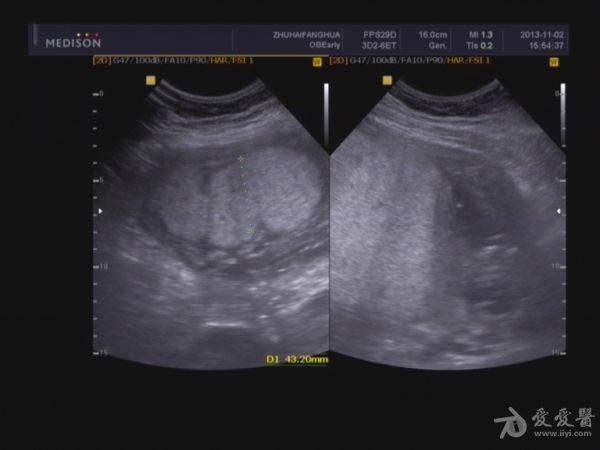

单胎妊娠;臀位,颅骨环基本完整,脑中线居中,CER: 24mm,CM:不清,双侧丘脑可见,侧脑室未见明显扩张,小脑可显示欠清,胎儿颈项部欠清,胎儿颜面显示不清,胸腔增大内见积液,腹壁完整,肝、可见,腹腔内大量积液,最大径约:71mm,胸腔内积液最大径:11.4mm,胃及膀胱显示不清。双肾显示不清。双侧四肢长骨显示欠清。

脐带:结构正常,脐动脉血流参数:SPV:33cm/s,PI:1.0,RI:0.62,S/D:2.6。典型图片如下: